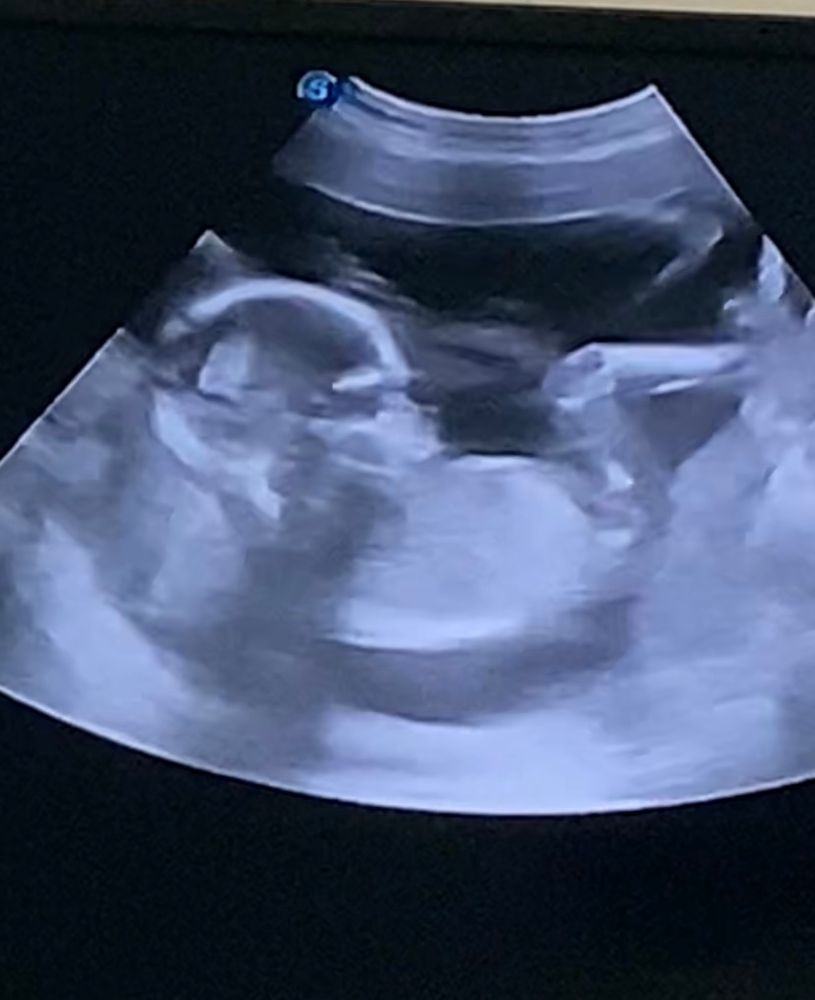

Гюлай в Благополучная беременность 2 года Скажите пожалуйста вы видите здесь пол ребенка? Пол малыша Посмотрите еще 20 записей на эту тему Отменить Ответить Кактусеныш Я вижу мальчика 21.02.2024 Ответить Кошка В Сапожках Мальчик 💙 21.02.2024 Ответить Ангелина Давыдова мальчик, поздравляю 🎉🎉🎉🎉🎉🎉🎉🎉 21.02.2024 Ответить Новикова Анастасия Егоровна кажется, что мальчик ✨✨ 21.02.2024 Ответить Сальникова Медина мальчик 😊😊 21.02.2024 Ответить vkook думаю мальчик 21.02.2024 Ответить Антонова Виктория как будто мальчик )) 21.02.2024 Ответить Приветик от малышки 👋🏻 Пол малыша Чаты Беременных Выберите чат: Январята-2026 Февралята-2026 Мартята-2026 Апрелята-2026 Майчата-2026 Июнята-2026 Июлята-2026 Августята-2026